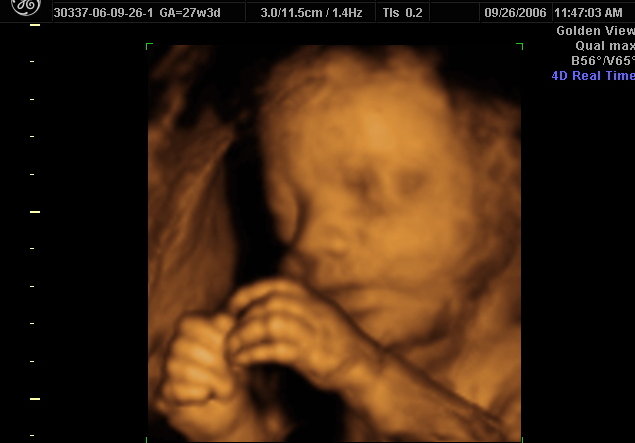

3d 4d ultrasound brooklyn. If you live in brooklyn or a neighboring community and would like to have a 3d ultrasound image of the child you are carrying call 1st glimpse inc. Over 150 google yelp reviews 718 844 2221. Goldenview ultrasound 3d4dhd nyc. Real time ultrasound is especially useful for imaging mobile subjects such as the fetus or heart and for quickly viewing an organ from different orientations.

2d 3d 4d ultrasound in brooklyn real time imaging is the most common sonographic technique used in obstetrics and gynecology. Office hours include weekdays evenings and weekends making it easy to accommodate your schedule. Reviews on 3d4d ultrasound in brooklyn ny 3d 4d ultrasound studio queens goldenview ultrasound 3d4dhd nyc 1st glimpse inc. Getting a 3d4d ultrasound in brooklyn during pregnancy for most moms a 3d4d ultrasound is or will probably be the first peek at their unborn child.

Here at 1st glimpse inc we have trained ultrasound technicians who will be able to provide both 3d and 4d ultrasounds showing exquisite images of the child growing in your womb.